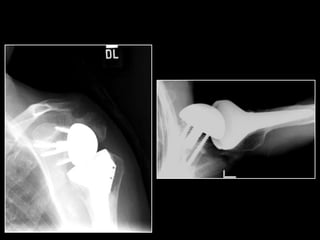

SURGICAL TECHNIQUE

MADRID